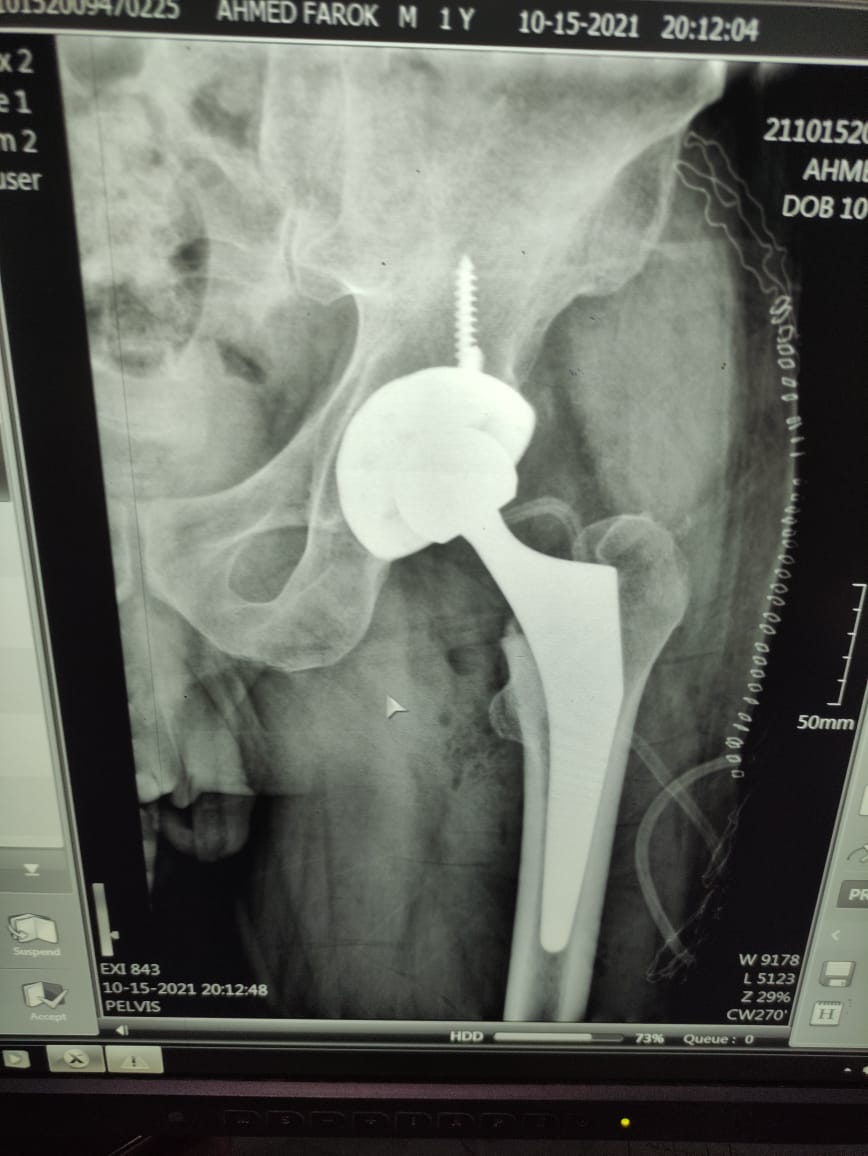

بتكلفة 80 ألف جنيه.. إجراء أول عملية تغيير مفصل بـ مستشفى بني سويف التخصصي

قال الدكتور صلاح عمر جودة، مدير عام مستشفى بني سويف التخصصي، إنه في إطار المبادرة الرئاسية للقضاء على قوائم الانتظار، تم ولأول مرة في مستشفى بني سويف التخصصي، إجراء عملية تغيير مفصل فخدي كامل لمريض  54 سنة مقيم مركز الواسطى ببني سويف، حيث أنه تم تحويل الحالة عن طريق الغرفة المركزية لقوائم الانتظار، بأمانة المراكز الطبية المتخصصة، وتم مناظرة الحالة بواسطة أطباء جراحة العظام بالمستشفى، واستكمال الفحوصات الطبية اللازمة ودللك لتحديد نوع المفصل المطلوب.

وأكد الدكتور صلاح عمر جودة، بأنه تم توفير المفصل المطلوب وإجراء الجراحة اللازمة للمريض، بتكلفة تتجاوز ثمانون ألف جنيه وتم إجراءها مجانًا للمريض.

وصرح الدكتور حمادة سعد، أخصائي جراحة العظام بالمستشفى، بأن المريض كان يعاني من خشونة متقدمة بمفصل الفخذ، وتم اجراء عملية تغيير لمفصل الحوض، وتركيب مفصل حوض لا أسمنتي والذي يتميز بأهميته في تقليل فترة العلاج بالمستشفى، وإمكانية حركة المريض من اليوم التالي للعملية.

وأضاف سعد، أن المريض سيتم وضعه تحت الملاحظة بالقسم الداخلي بالمستشفى للمتابعة واستكمال العلاج لمدة يومين على أن يبدأ جلسات العلاج الطبيعي بالمستشفى بعد ثلاثة أسابيع من الجراحة.